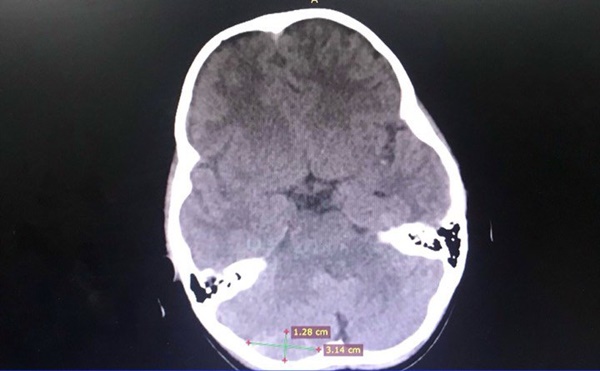

Sau khi nhập viện kiểm tra và theo dõi, bé T được phát hiện bị máu tụ ngoài màng cứng hố sau bên phải. Ngay lúc này, bé được chỉ định can thiệp lấy máu tụ để giải ép do các bác sĩ khoa Ngoại Thần Kinh phối hợp với các bác sĩ hồi sức Nhi, bác sĩ gây mê tiến hành.

Hình ảnh máu tụ trong não bé trước phẫu thuật.

BS.CKI. Trương Long Vỹ - Trưởng khoa Ngoại Thần Kinh - phụ trách chính ca phẫu thuật chia sẻ: “Thông thường, máu tụ ngoài màng cứng hố sau rất nguy hiểm, cần phải được quyết định can thiệp nhanh chóng và kịp thời, tránh tình trạng gây chèn ép tụt não, ảnh hưởng đến tính mạng bệnh nhân. Đặc biệt ca phẫu thuật lần này trên bệnh nhân nhi 5 tuổi cần sự tỉ mỉ, chính xác và dụng cụ phải phù hợp. Nếu như bệnh nhân không được phát hiện sớm, mổ kịp thời thì bệnh nhân có thể rơi vào tình trạng nguy hiểm. Cuộc phẫu thuật kéo dài trong 1 giờ và theo dõi sau mổ bệnh nhân đã hồi phục.”